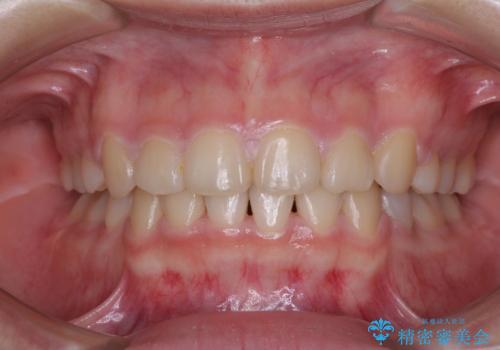

舌の突出癖があり、咬合力も強かったため、治療期間は長くなることが懸念されましたが、舌のトレーニングをしっかりと行っていただいたこともあり、2年弱で治療を終えることができました。

上下ともに歯列が前方に突出していたため、上下左右の第一小臼歯4本を抜去する方針(既に上顎は抜歯されています)で、ワイヤー装置による矯正治療を行うこととしました。

舌の突出癖による影響もあったため、舌のトレーニングを並行して実施しました。